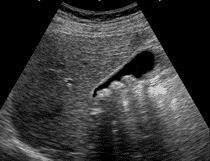

Dass diese Artefakte keine Gallensteine sein können, lässt sich durch eine Schwimmprobe erkennen: Die bei dieser Methode beobachteten Konkremente schwimmen nämlich auf dem Wasser, während dies tatsächlich nur für einen Teil der Gallensteine zutrifft. Echte Gallensteine sammeln sich daher in der Regel am Boden der Gallenblase, wo sie im Röntgen- oder Ultraschallbild gesehen werden können. Einige Formen von Cholesterinsteinen können in hochkonzentrierter Galle in der Gallenblase aufschwimmen. Ein weiterer Beweis, dass diese Konkremente nicht Steine aus der Gallenblase sein können, ergibt sich aus Beobachtungen der erzielbaren Konkrementmengen (bis zu 500 oder gar 1000 Stück), die niemals in einer Gallenblase Platz fänden.[5] Die Gallenblase eines Erwachsenen ist nur wenige Zentimeter lang und hat ein Fassungsvermögen von etwa 50 Milliliter.

Der Internist Nils Ewald vom Universitätsklinikum Gießen veröffentlichte im September 2009 eine Mitteilung an die Deutsche Medizinische Wochenschau,[17] in der er über einen 59-jährigen Mann berichtete, der sich mit einer derartigen Leberreinigung selbst zu therapieren versuchte. Der Mann war beschwerdefreier (asymptomatischer) Gallensteinträger und führte alle vier Wochen eine derartige Leberreinigung mit Olivenöl und Grapefruitsaft durch. Jedes Mal fanden sich im Stuhl gallensteinähnliche Konkremente. Wegen einer möglichen "massiven Neigung zu Gallenstein" wurde er vom Hausarzt in die Gastroenterologie der Uniklinik Gießen eingewiesen. Bei der Ultraschalluntersuchung der Gallenblase fanden sich nach wie vor Gallensteine in gleicher Anzahl. Die vom Patienten zur Verfügung gestellten Konkremente wurden chemisch untersucht und eindeutig als Nicht-Gallensteine identifiziert. Es fehlte die typische kristalline Struktur sowie die gallensteintypischen Bestandteile. Hingegen fanden sich Fettsäuren als Reaktionsprodukt der aufgenommenen Lebensmittel Olivenöl und Fruchtsaft. Bei (mit Ultraschall nachgewiesenem) Fehlen eigener Gallensteine schieden Ewald und zwei seiner Kollegen in einem Selbstversuch ebenfalls die entsprechenden "Steinchen" aus.[18]

2010 war die Leberreinigung Thema im deutschsprachigen Schweizer Fernsehen SF (Sendung "Puls"). Die Mitarbeiterin Sarah Allemann des SF ließ sich per Ultraschall untersuchen. Das Ergebnis war, dass bei ihr keine Gallensteine auffindbar waren. Anschließend testete sie die "Leberreinigung" und trotz nicht vorhandener Gallensteine zeigten sich bei ihr die grünen Steinchen in der WC-Schüssel. Das Fernsehteam brachte die Steine ins Labor am Institut für Klinische Chemie des Universitätsspitals Zürich. Eine Untersuchung mittels Röntgendiffraktion zeigte, dass die Steine keine kristallinen Komponenten enthielten, was bei echten Gallensteinen zwingend der Fall sein müsste. Unter einer wärmenden Lampe wurden die Klumpen weich und zerflossen. In einer weiteren Laboranalyse wurde die genaue Zusammensetzung aus verseifter Ölsäure vom Olivenöl nachgewiesen.[19]

Unter Berufung auf die verstorbene US-amerikanische Scharlatanin Hulda Clark bietet der in Bayern lebende deutsche Arzt Georg Kneißl eine Anleitung zur Reinigung der Leber als eine der Varianten der hier thematisierten Leberreinigung an.[20] Wünschenswert sei "vorab die Zahnsanierung mit einer Entfernung aller Amalgamfüllungen", denn "ein toxischer Mund ist für die Leber stets eine schwere Belastung". Von der österreichischen Firma SAN-U-VIT GmbH aus St. Johann im Pongau wird ein Set mit den zusätzlich zum Olivenöl notwendigen Substanzen ("Epsom Salz, Power C, Korianderwürze nach Dr. G. Kneißl 50ml, Liver-Vit, L-Ornithin, Vitamin E Premium Komplex") verkauft, das Kneißl wie folgt bewirbt: "Reinigen Sie Ihre Leber wenigstens zweimal im Jahr! .. Gratulation! Sie haben Ihre Gallensteine ohne Operation entfernt und haben massiv Gifte, Bakterien und Viren ausgeschieden!!". Kneißl unterschlägt, dass eventuell vorhandene Gallensteine, die keine Symptome verursachen, in der Regel nicht entfernt werden müssen. Auch fordert er keinerlei Nachweis des Vorhandenseines etwaiger Gallensteine für seine Methode. Im Gegenteil: nach Kneißl sei der medizinisch anerkannte Weg, tatsächliche Gallensteine nachzuweisen, untauglich. Zitat: "Wenn die Gallenblase mit Ultraschall untersucht oder geröntgt wird, ist oft nichts zu sehen." Tatsächlich erreicht eine herkömmliche Ultraschalluntersuchung beim Nachweis von Gallensteinen eine Treffsicherheit von mehr als 95 Prozent.